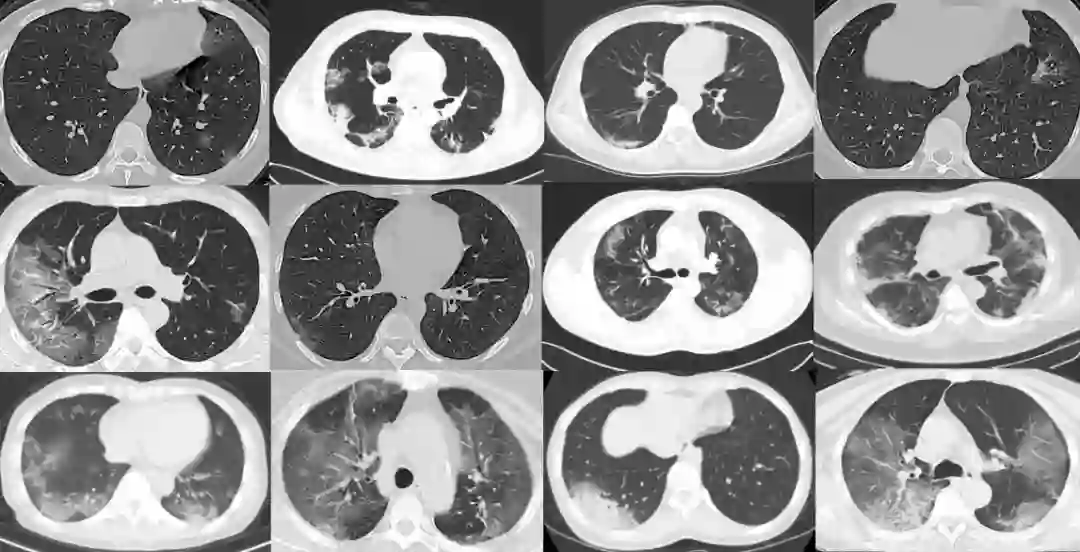

最终他们获得了 275 个 CT 扫描图像,标记为新冠肺炎阳性。这些图像大小不同:最小、平均和最大高度分别为 153、491 和 1853;最小、平均和最大宽度分别为 124、383 和 1485。这些扫描来自 169 例患者。图 1 显示了新冠肺炎 CT 扫描图像的一些示例。

图 1:新冠肺炎呈阳性的 CT 扫描图像示例。